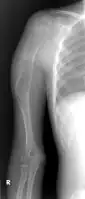

| X-ray knee - chondromyxoid fibroma in long bone of thigh near the knee | |

Chondromyxoid fibroma is a non-cancerous cartilaginous tumor, a type of bone tumor.[2][4] It usually presents with pain and swelling in a long bone of the leg in an adolescent.[1][3]

It is rare, comprises <1 % of all bone tumors that arise from bone itself and <2% of cartilage tumors.[2] Around half occur around the knee and mostly in long bone of lower leg in the teens.[2]